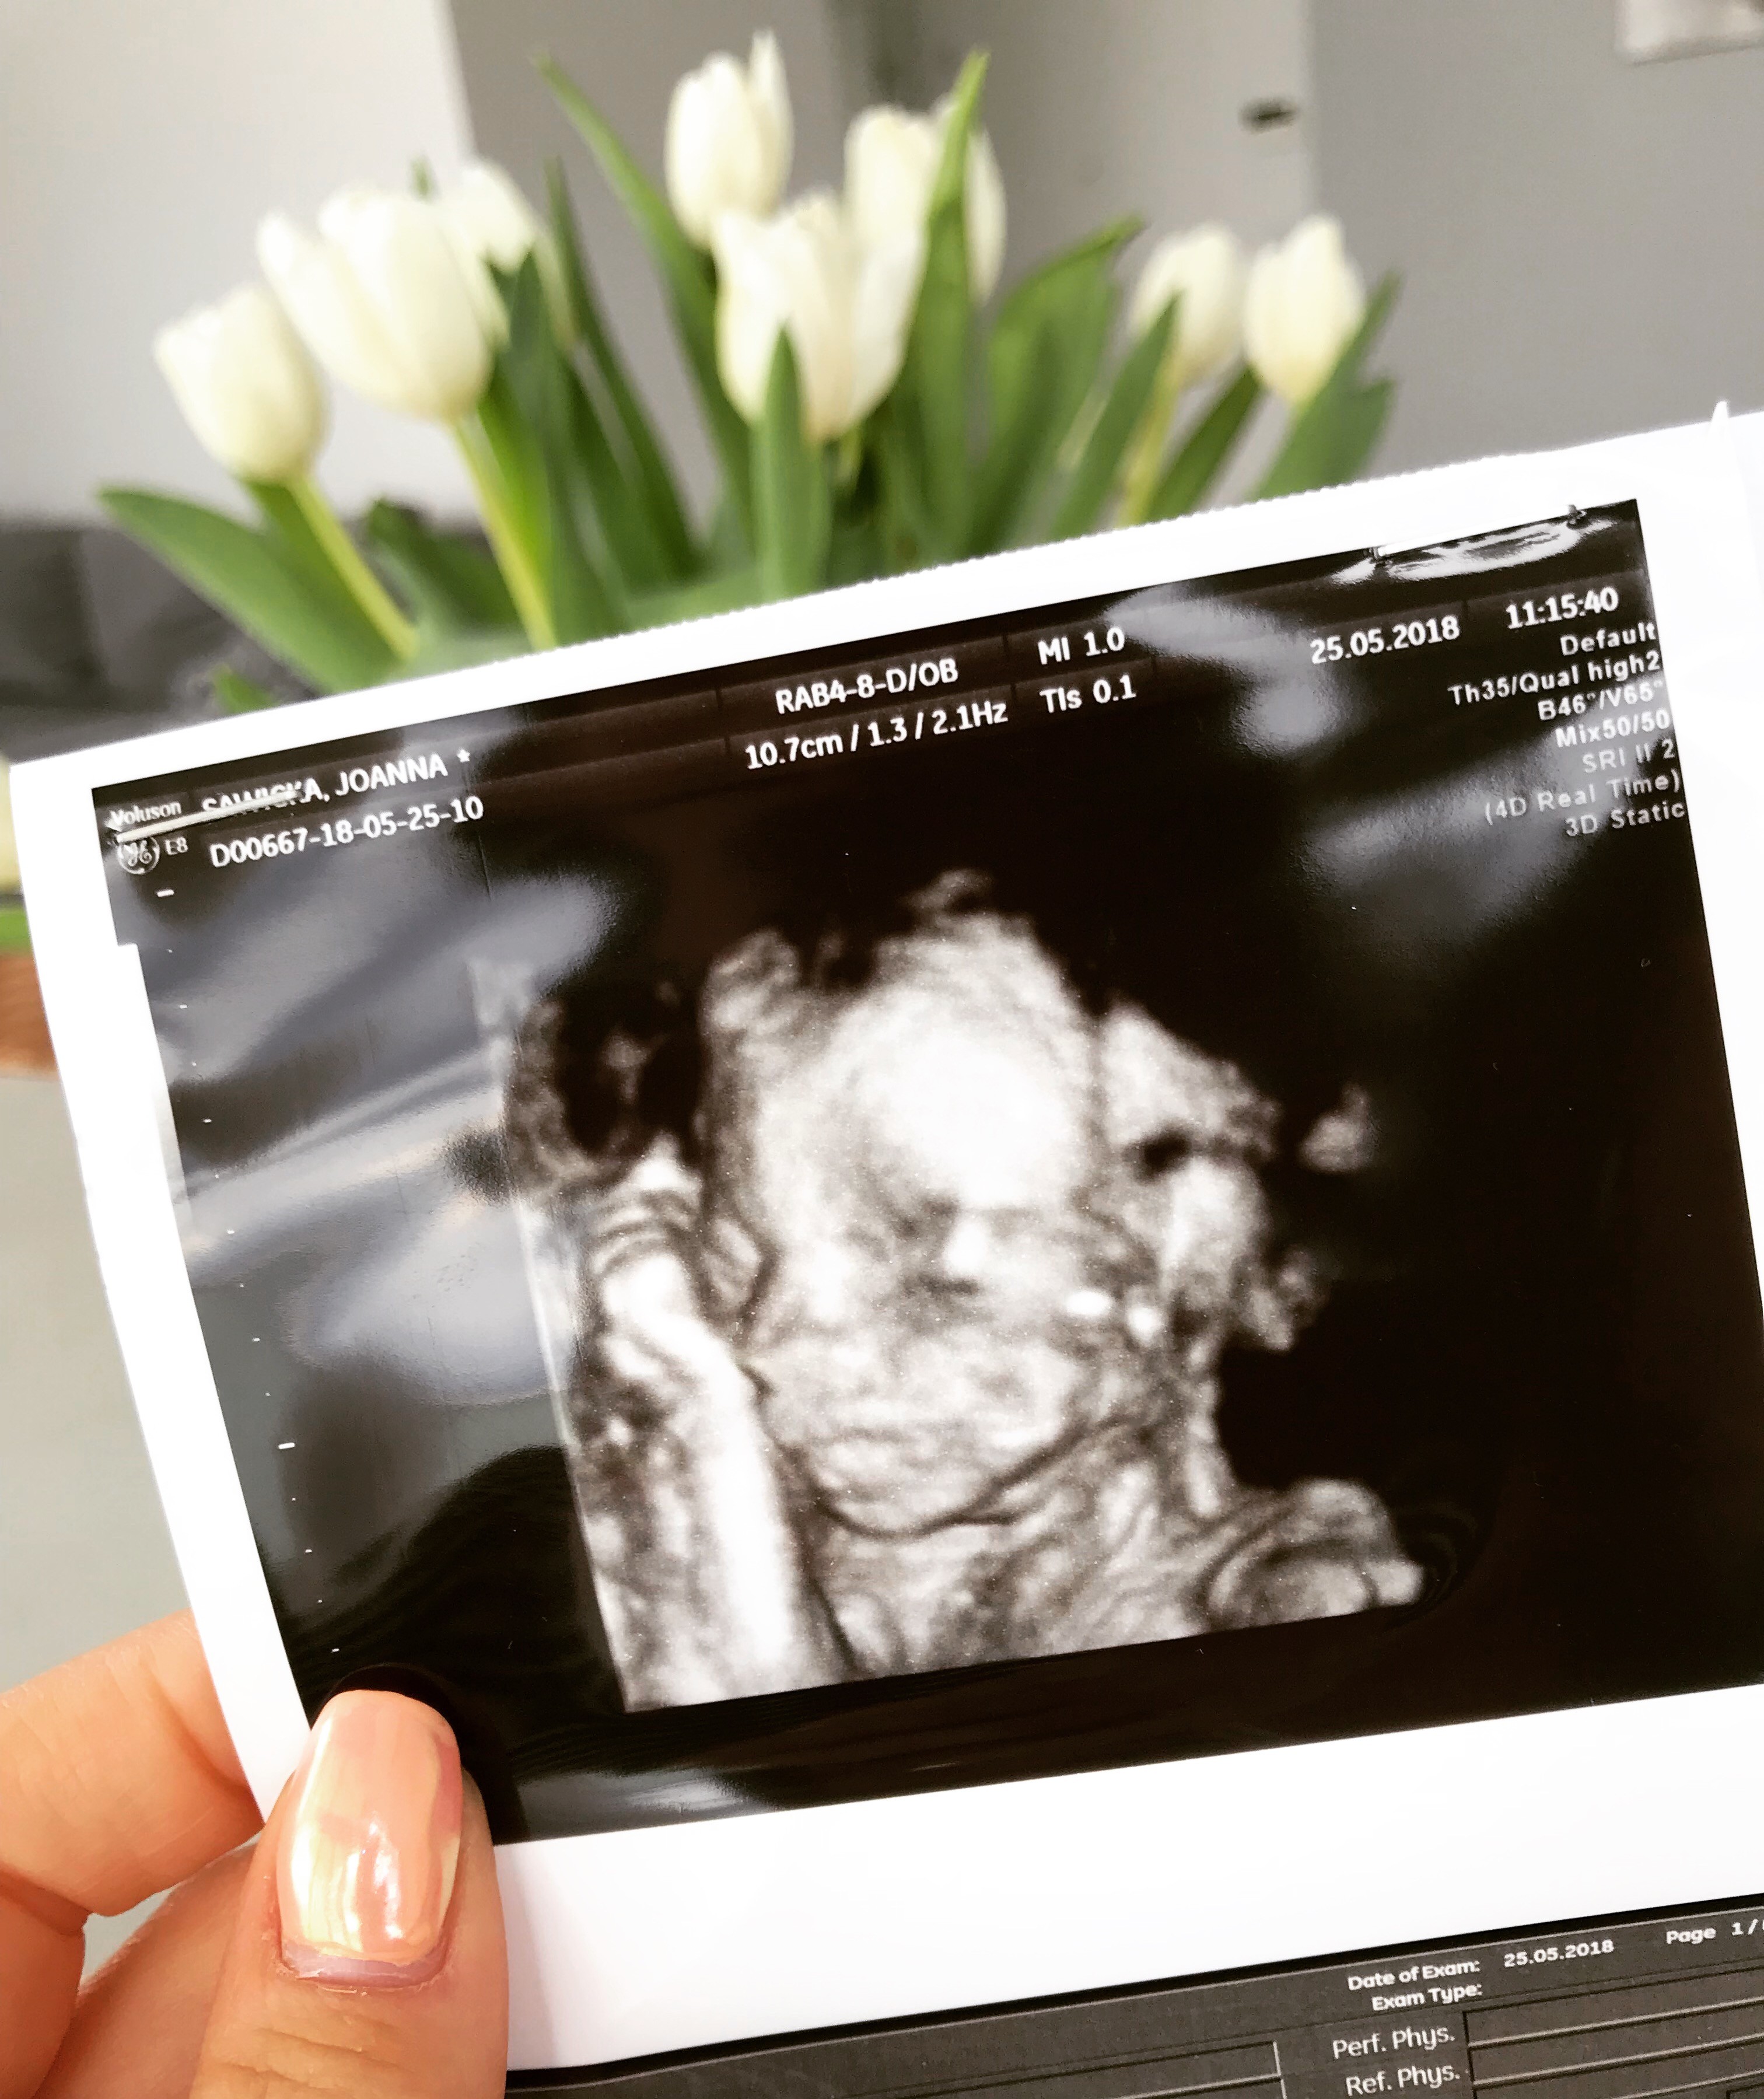

Zobacz załącznik 860272

to ja coś równie śmiesznego załączam [emoji23]

Haha, mnie to rozwaliło